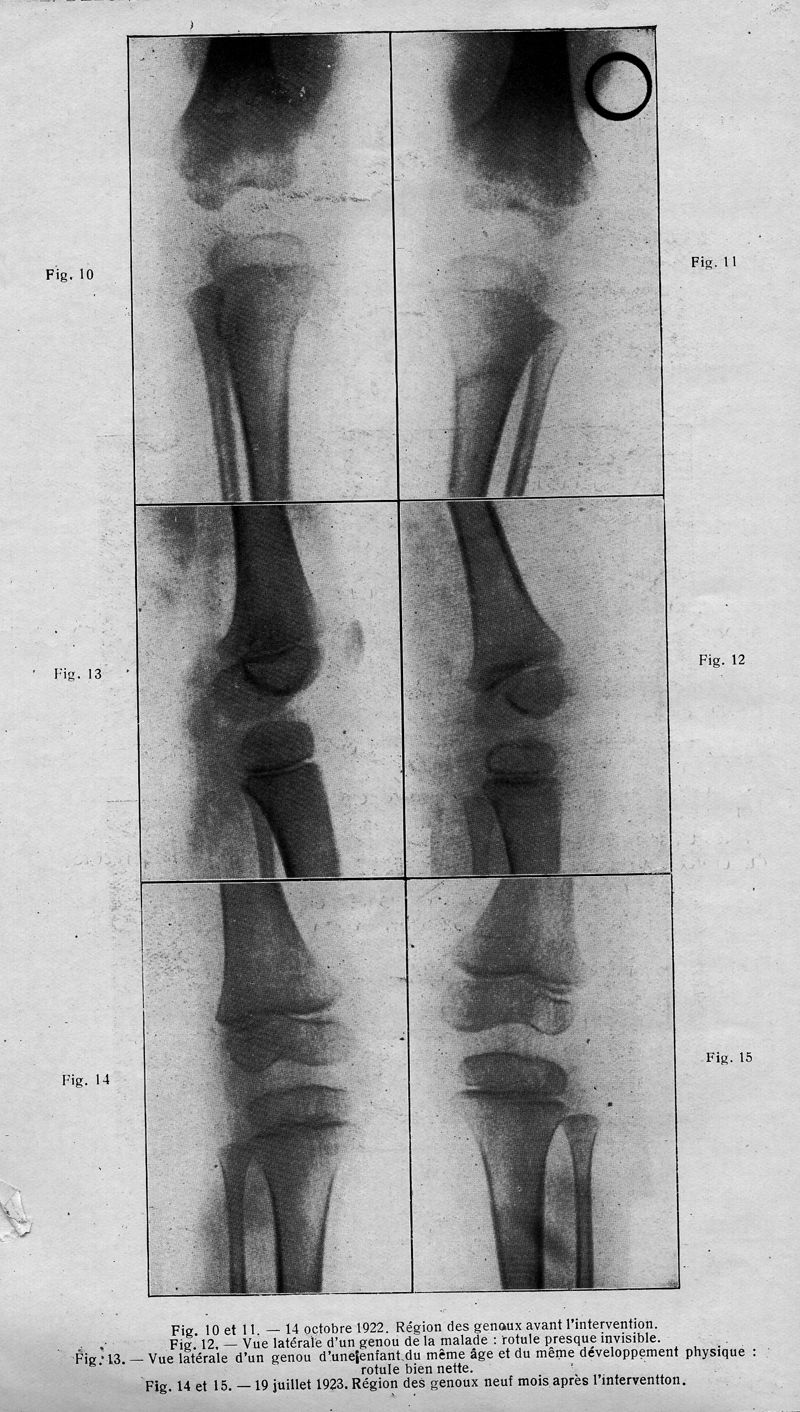

In : Archives franco-belges de chirurgie, 1924, Vol. 27, pp. 238-40